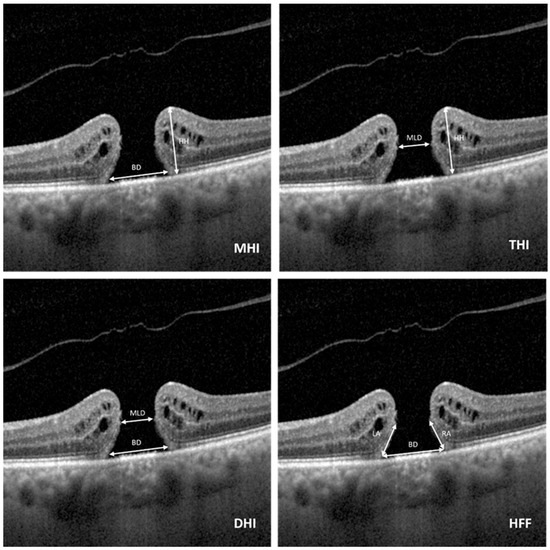

Predictive Value of Preoperative Anatomical and Functional Parameters for Long-Term Visual Outcomes After Full-Thickness Macular Hole Surgery with the Inverted Flap Technique

Background/Objectives: The aim of the present study was to identify preoperative functional and anatomical parameters that better predict postoperative best corrected visual acuity (BCVA) after full-thickness macular hole (MH) surgery during long-term follow-up. Methodology: Initial visual outcomes, medical history, retinal imaging data, microperimetry [...] Read more.

Background/Objectives: The aim of the present study was to identify preoperative functional and anatomical parameters that better predict postoperative best corrected visual acuity (BCVA) after full-thickness macular hole (MH) surgery during long-term follow-up. Methodology: Initial visual outcomes, medical history, retinal imaging data, microperimetry and mfERG measurements were collected to characterise functional and morphological macular status. Results: Among the study subjects, 22 presented with a BCVA > 0.5, and 20 presented with a BCVA ≤ 0.5 at the final visit. Multivariate regression analysis revealed that a smaller minimum MH diameter (OR = 0.98; 95% CI = 0.87–0.99; p = 0.004) and a shorter disease duration (OR =0.11; 95% CI = 0.02–0.53; p = 0.005) were predictors of postoperative long-term BCVA > 0.5. Baseline P wave amplitudes in the central ring on mfERG were positively correlated with postoperative BCVA gain (Rs = +0.53, p = 0.001). Conclusions: Our findings corroborate the significance of hole diameter measurements for postoperative visual outcomes and support the rationale of early intervention. Full article